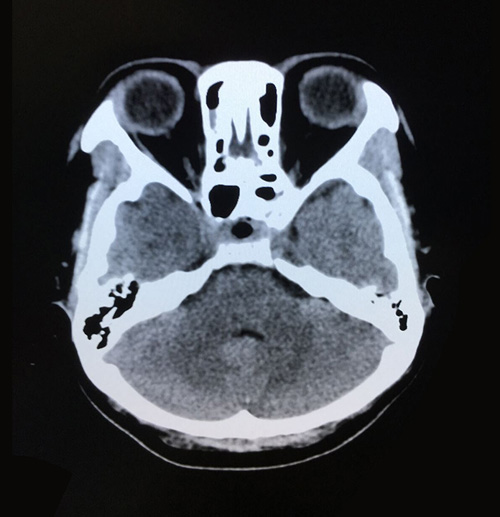

術(shù)后影像:兩側(cè)大腦,小腦及腦干形態(tài)如常,腦溝腦池未見異常

認(rèn)真休養(yǎng)一周之后,鄭鈺玲老師身體恢復(fù)很快,在出院前,她和愛人為醫(yī)護(hù)人員送上鮮花表示感謝。一轉(zhuǎn)眼,求醫(yī)幾個(gè)月,學(xué)校的校領(lǐng)導(dǎo),鄭鈺玲老師的學(xué)生和女兒都在等著她回去。今年可以一家人開心健康的過春節(jié),年后鄭鈺玲老師又可以登上心愛的講臺(tái)啦。